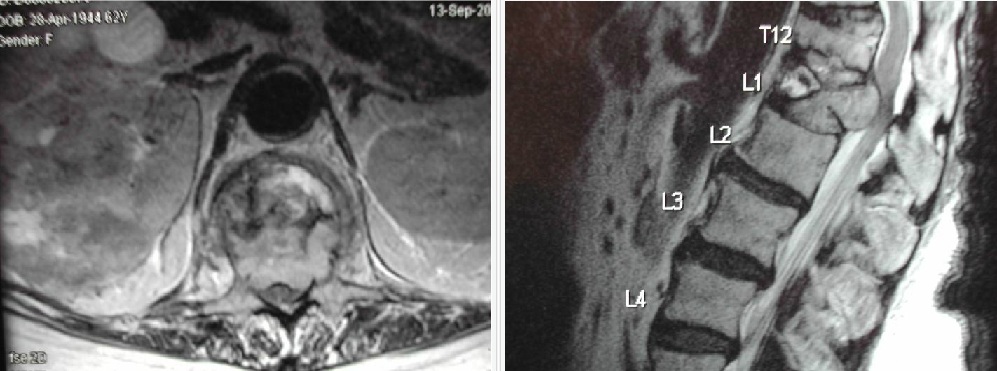

22 tahun menderita cedera tulang belakang setelah jatuh dengan burst fraktur L2 dan canal compromise. Lebih dari setengah dari otot-otot di bawah tingkat cedera memiliki tingkat kekuatan

A. C The correct answer is ASIA C. According to the current (2000/2002 ASIA Standards) the patient meets the criteria for an incomplete spinal cord injury with a “C” classification. As stated, “Motor function is preserved below the neurological level, and more than half of the key muscles below the neurological level have a muscle grade less than 3.” A—Complete injury. No sensory or motor function is preserved in the sacral segments S4-S5. B—Incomplete. Sensory but not motor function is preserved below the neurological level and includes the sacral segments S4-S5. D—Incomplete. Motor function is preserved below the neurological level, and at least half of the key muscles below the neurological level have a muscle grade greater than or equal to 3. E—Normal. Sensory and motor functions are normal.